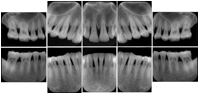

OO.1.2 Ophthalmology

1. A patient in rural Canada visits a general ophthalmologist and is found to have diabetic macular edema. The general ophthalmologist would like to discuss the case with a retina specialist before performing laser surgery. A fluorescein angiogram is done with multiple retinal images taken in a timed series after an intravenous injection. The images along with a Structured Display are shared via a Health Information Exchange with a retina specialist in Calgary, who opens them using his Ophthalmology EMR software and consults via phone with the general ophthalmologist. Both physicians view the images in the same layout so the retina specialist can provide accurate guidance for treating the patient.

2. A patient in rural Iowa visits his primary care physician for management of diabetes. Three non-mydriatic (patient's eyes are not dilated) photographs are taken of the back of each eye, and forwarded electronically along with a Structured Display to an ophthalmologist in Iowa City. The ophthalmologist reads the photos in an agreed upon layout so there is no mistake about what portion of which eye is being viewed. The ophthalmologist is able to tell the primary care physician that his patient does not need to come to Iowa City for face to face ophthalmologic care, but that there is a particular view of the left eye that should be photographed again in 6 months.

Ophthalmic Retinal Study Structured Display

Figure OO-3. Ophthalmic Retinal Study Structured Display